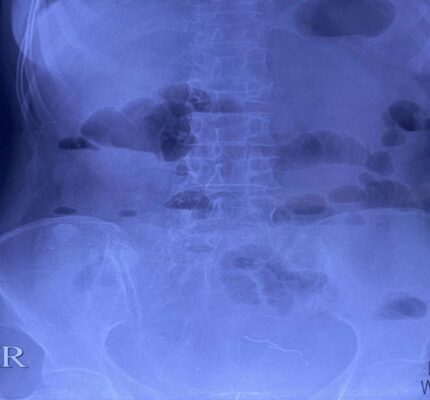

Hình 1: X-quang bụng không chuẩn bị: Phát hiện dị vật dạng kim loại nằm ở vùng tiểu khung trái, không thấy liềm hơi dưới cơ hoành.